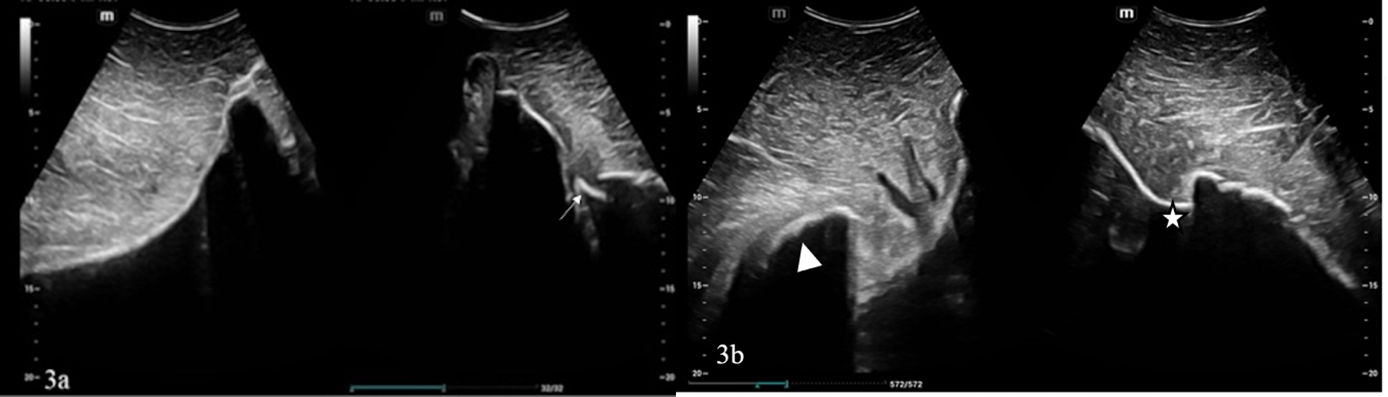

El examen ecográfico externo de la hemipelvis izquierda mostró una fractura aguda, completa y desplazada (aproximadamente 7 cm) en el margen caudal del ala ilíaca izquierda y de la cara craneal del cuerpo ilíaco (figuras 2). El examen de la hemipelvis derecha también evidenció una fractura desplazada del ala ilíaca derecha, ubicada más cerca del plano medio que la izquierda. El contorno del hueso ilíaco derecho se presentó más liso, irregular y grueso; estas características sugerían cambios de remodelación ósea crónica (figuras 3). El abordaje ultrasonográfico transrectal reveló un hematoma ventral y un fragmento óseo a la altura de la articulación sacroilíaca derecha (figuras 4).